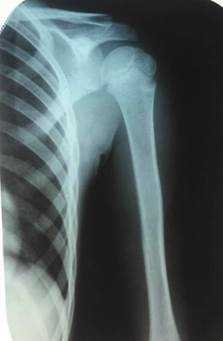

У детей возрастной группы от 3 до 17 лет на 5-7-е сутки болезни рентгенологически деструктивных костных изменений не определялось. Первые рентгенологические проявления в виде увеличения объема и плотности мягких тканей, линейного периостита, нечеткости костной структуры, утолщения и разрыхления коркового слоя отмечались в среднем на 10-14-е сутки (n=43; 39%). Периостит, разрыхление коркового слоя, остеопороз и остеосклероз, деструкция определялись на более поздних сроках. Таким образом, рентгенография не может рассматриваться в качестве метода диагностики остеомиелита на ранних сроках (рис. 1).

Рис. 1. Острый гематогенный остеомиелит плечевой кости - 11-е сутки заболевания